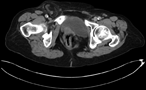

Acute abdomen due to an infected urachal cyst in a 5-year-old female: case report

Aghyad Kudra Danial and others

Journal of Surgical Case Reports, Volume 2019, Issue 5, May 2019, rjz156, https://doi.org/10.1093/jscr/rjz156